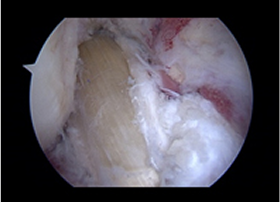

5mm정도의 피부절개를 통해 초소형 카메라와 수술 도구가 부착된 내시경을 관절 내부로 삽입하여

정확한 병변을 먼저 확인한 후 적절한 치료 방법을 결정하여 병변을 제거하거나 복원합니다.

관절내시경 수술 장면

절개가 거의 없어 최소 침습적 수술이 가능하지만, 제한된 공간에서 시행되므로 난이도가 높은 경우가 많아 반드시 숙련된 내시경 전문의에게 시술을 받아야 만족스러운 결과를 얻을 수 있습니다.